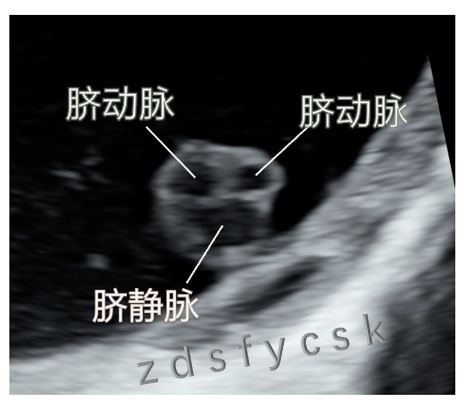

脐带连接着胎儿和母体,是母体和胎儿血液循环的纽带。正常脐带内有两条脐动脉和一条脐静脉。当脐带内只有一条脐动脉和一条脐静脉的时候,称为单脐动脉。

正常脐动脉